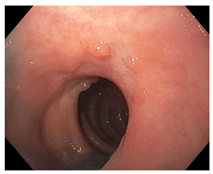

| Endoscopy | Flat white scar Telangiectasia Absence of ulcers and mucosal nodularity | Small mucosal nodules/minor mucosal irregularities Superficial ulceration Mild, persistent erythema of the scar | Visible tumor |

| Flat, white scar | ![]() | ![]() | ![]() |

| Telangiectasia | ![]() | ![]() | ![]() |